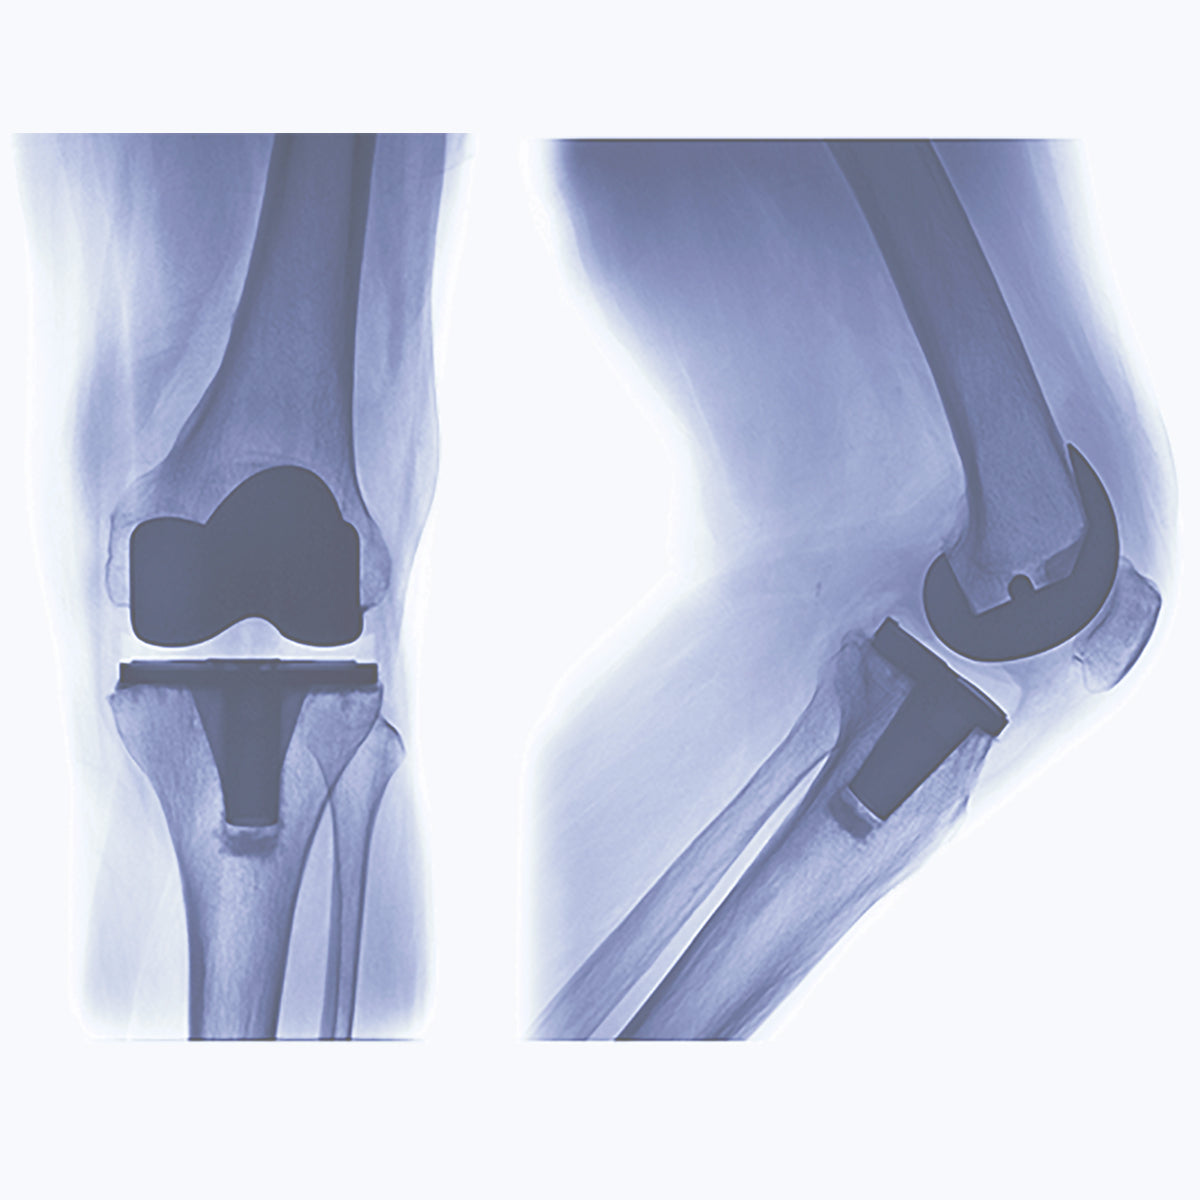

Pre- and Post-Surgery Rehabilitation

Pre- and post-surgery restricted movement can result in atrophy and compensatory muscle imbalances in the affected area and in other parts of the body.

Pre-surgery symptoms are usually pain and restricted movement caused by damaged tissue, which can also restrict movement in other areas of the body. Post-surgery symptoms are usually pain and restricted movement caused by the surgical trauma, which can also restrict movement in other areas of the body.

Surgery is required when the lower limb and back are sufficiently injured or there is a genetic defect that cannot be corrected by other means.